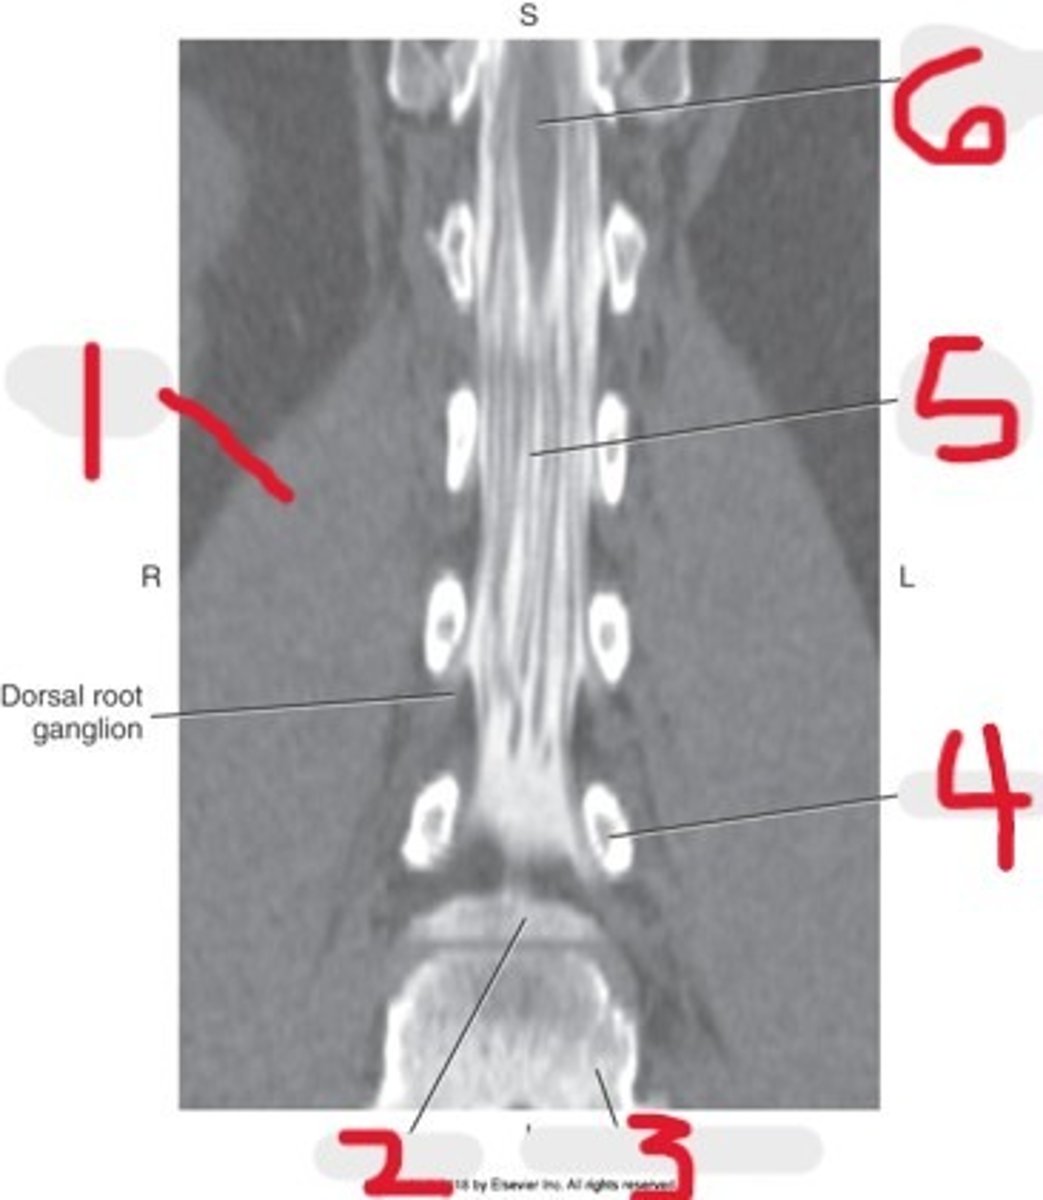

1) Conus medullaris

2) Cauda equina

3) Thecal sac

Name all numbered structures

1) L5

2) Sacrum

3) Conus medullaris

4) Cauda equina

5) Subarachnoid space with contrast

Name all numbered structures

1) Psoas muscle

2) Cauda equina

Name all numbered structures

1) Psoas muscle

2) Vertebral body

3) Cauda equina

Name all numbered structures

1) Right Psoas muscle

2) Body of L5

3) Sacral promontory

4) L4 pedicle

5) Cauda equina

6) Conus medullaris

Name all numbered structures

1) Sacrum

2) Conus medullaris

3) Cauda equina

Name all numbered structures